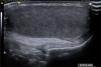

Varón de 12 años derivado por asimetría testicular detectada en revisión de salud (teste izquierdo de 9ml y derecho de 5ml con orquidómetro). Se solicita una ecografía testicular, donde se observa un testículo derecho normal (fig. 1). En el escroto izquierdo destacan 2 imágenes ovoides, isoecogénicas y homogéneas, una craneal de 1,3ml y otra distal de 4,8ml (fig. 2). Ambas tienen una zona central hiperecogénica (hilio testicular) con margen hiperecogénico fino (túnica albugínea) (fig. 3). Se diagnostica de poliorquidismo o testículo supernumerario izquierdo.

Generalmente el signo guía es una masa escrotal asintomática. La prueba de primera elección es la ecografía, que muestra un teste supernumerario con ecoestructura normal y doppler conservado, normalmente de menor tamaño que el teste contralateral.